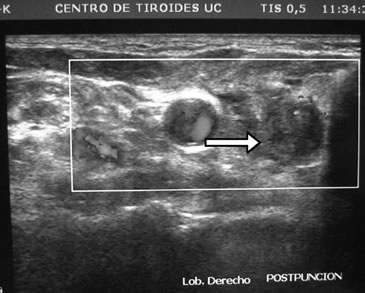

Desde el punto de vista bioquímico sus controles en los últimos 10 años mostraban normalidad de la calcemia y fosfemia. A los 76 años es estudiada en nuestro servicio donde se constata hiperparatiroidismo secundario de doble etiología: hipovitaminosis D e hipercalciuria renal. Sus exámenes de sangre, sin mediar tratamiento, eran: Ca: 9,3 mg/dL; P: 3,5 mg/dL; albúmina: 4,4 g/dL; fosfatasas alcalinas: 78 U/L; PTH: 90,9 pg/mL (VN: 15-65 pg/mL); 25OHD: 10 ng/mL (VN: 20-40ng/ml) y creatinina normal. En orina: Ca: 326 mg/24h; creatinina: 0,92g/24h; Ca/Creat: 0,35. La paciente había sido tratada con dosis bajas de levotiroxina (50 ug/d) y controlada con ecografías cervicales debido a hipotiroidismo subclínico (TSH: 7,1 uUI/mL) detectado a los 69 años, con varios nódulos tiroideos en ambos lóbulos de características coloideas y estables. El mayor de ellos estaba en el polo inferior del lóbulo derecho y medía 8 x 6,5 x 4 mm. Repetido el estudio 1 mes después con un ecógrafo de 12,5 MHz se agrega a la descripción anterior, bajo maniobra de compresión zonal, un nódulo ovalado, de 7,8 mm de diámetro mayor, hipoecogénico, homogéneo, de limites difusos, ubicado en posición retrotiroidea del polo inferior derecho, visualizándose al doppler vasos de entrada y salida con abundante circulación intranodal (Figura 2a). Se efectuó punción con aguja fina (PAF) obteniendo buena muestra, pero el procedimiento se complica con sangramiento (Figura 2b). El informe histopatológico certifica células paratiroideas de aspecto normal,lo que se corrobora con la positividad de la tinción inmunohistoquímica con anticuerpos monoclonales para PTH, según técnica S-ABC.

Comentario especial merece el estudio ecográfico de las glándulas paratiroideas, en que la técnica no corresponde a la simple extensión de la usada en el diagnóstico de nódulo tiroideo. Para el estudio ecográfico de las glándulas paratiroides es importante ejercer presión con el transductor sobre los tejidos cervicales, para acercar las glándulas paratiroides al foco del transductor, y así poder obtener imágenes de ellas. De lo contrario, la distancia habitual entre transductor y glándula paratiroidea es tal que disminuye notoriamente la sensibilidad de la búsqueda. Otra forma de optimizar la visión ecográfica es agregando un baño de agua, dado que la conducción acústica es óptima en medio líquido; en nuestro caso, el hematoma derivado de la PAF generó espontáneamente un medio acuoso, lográndose una clara visualización de la glándula paratiroides, desapercibida en los exámenes anteriores (Figura 2b).